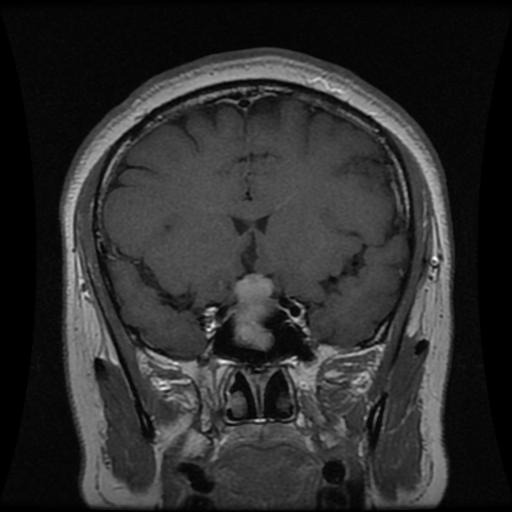

Figure 2: Samples of Meningioma segmentation across different imaging planes

Meningioma: Meningiomas arise from the meninges and are generally well‑circumscribed and homogeneous, making them easier to segment. However, their location adjacent to critical structures such as dural sinuses and cranial nerves can complicate diagnostic tasks. An example of a meningioma and its segmentation mask is presented in Figure 2, illustrating the clarity of its boundaries.